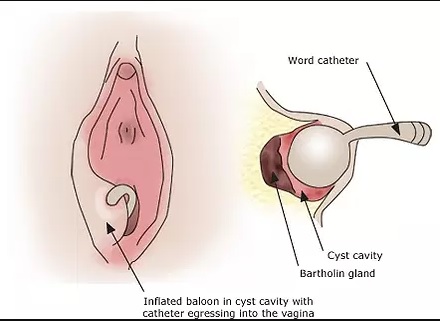

BARTOLİN BEZİ APSESİ NEDİR? NASIL TEDAVİ EDİLİR? Bartolin bezi vajinanın iki tarafında bulunan ve vajinaya salgı ü...